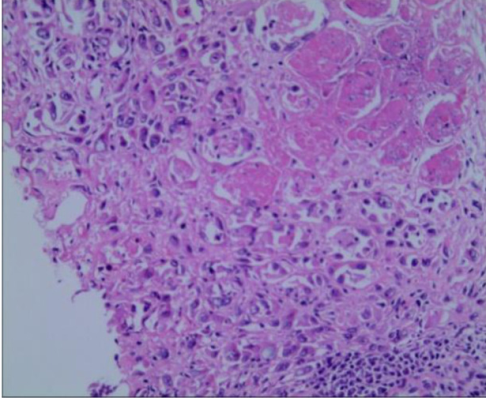

α) Νεκρωτική αγγειίτιδα. Διατοίχωμα φλεγμονή του αγγειακού τοιχώματος, με ή χωρίς ινοειδή νέκρωση. β) Νεκρωτική αγγειίτιδα μεσεντερικής αρτηρίας, με παναρτηριακή νέκρωση και παρουσία ινοειδούς νέκρωσης αγγειακού τοιχώματος. Ευγενική παραχώρηση Dr. V. Penopoulos.